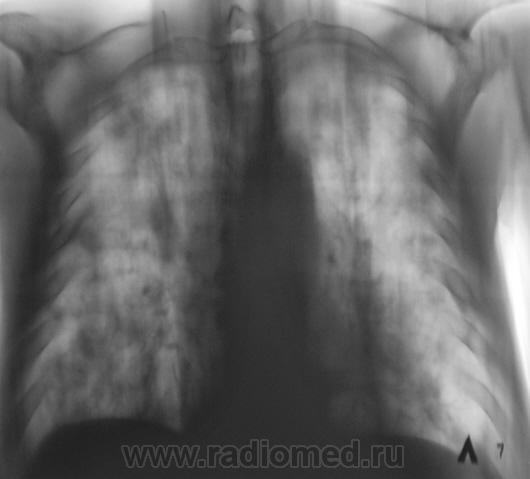

Молодая девушка взята на контроль, дообследована.

Рентгенограмма.

[[wysiwyg_imageupload:577:]]